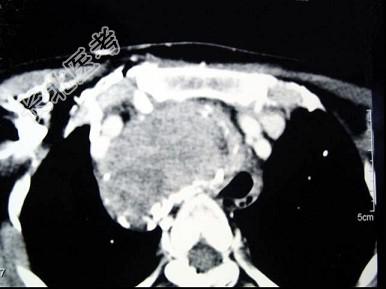

- 多项选择题女,48岁, 颈部包块3年,近来胸闷、憋气、胸痛, CT扫描如图,正确的描述或诊断是 ( )

A、胸骨后甲状腺肿

C、双侧甲状腺肿大

D、胸骨后甲状腺肿是指甲状腺50%位于胸骨后

E、胸骨后甲状腺肿是指甲状腺60%位于胸骨后